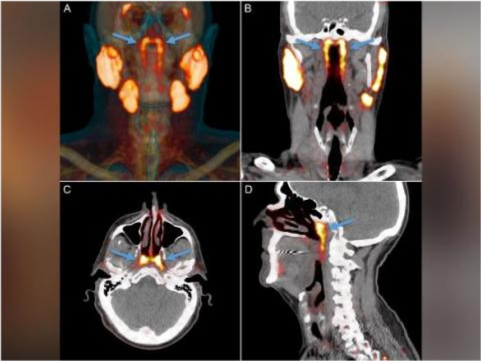

据美国有线新闻网(CNN)报道 , 来自荷兰的几名科学家发现了以前未被觉察到的一对腺体 , 这种器官隐藏在人类头骨中鼻腔和喉咙的交汇处 。

瓦尔斯塔说 , 传统的医学成像技术 , 例如超声、CT扫描或MRI(磁共振成像)是看不到这些腺体的 。 当医生使用一种名为PSMA PET/CT的先进的新型扫描技术来检测前列腺癌的扩散时 , 这个“未知实体”才被发现 。